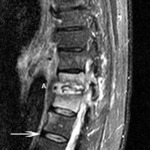

ლიმფომის მაგნიტური-რეზონანსული ტომოგრაფია: ისრის წვერი მიუთითებს რბილქსოვილოვან წარმონაქმნზე, რომელიც იჭრება ხერხემლის არხში. ისარი მიუთითებს სიმსივნეზე, პროტრუზიით L5 მალის სხეულის წინ

ექიმ Dr K. Singh საკუთრება; გამოყენებულია ნებართვით